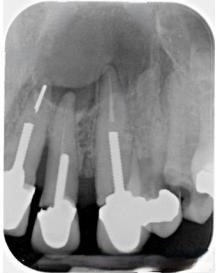

Perforación Radicular

Una perforación radicular es una abertura anormal en la raíz del diente, generalmente debido a un procedimiento dental fallido o una caries profunda.

Los pacientes pueden sentir dolor y notar hinchazón en la encía.

El tratamiento incluye la reparación de la perforación y el tratamiento de conducto. Es crucial reparar la perforación para evitar una infección.